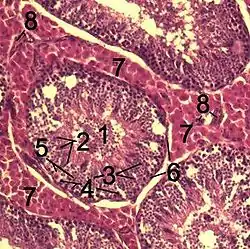

![]() Histological section through testicular parenchyma of a boar. 1 Lumen of convoluted part of the seminiferous tubules, 2 spermatids, 3 spermatocytes, 4 spermatogonia, 5 Sertoli cell, 6 myofibroblasts, 7 Leydig cells, 8 capillaries | |